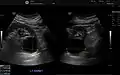

Renal cyst as seen on abdominal ultrasound